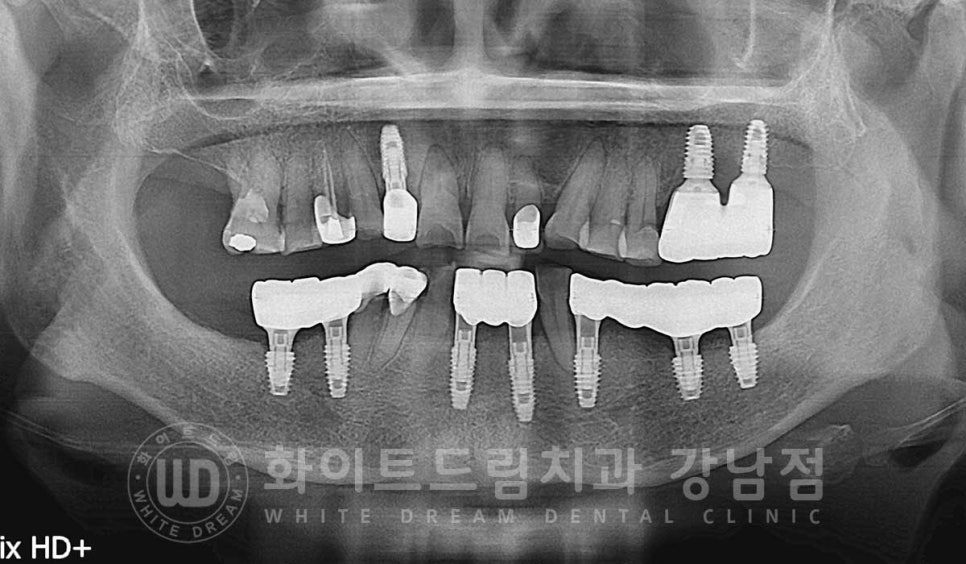

상실된 하악 치아들은 임플란트로 대체하면서

상악 염증으로 흔들리는 12번 치아도 함께 치료를 진행하기로 했는데요.

하악 임플란트는 하악 턱뼈 안을 지나가는 신경을 항시 주의하며

치료를 진행해야 합니다.

치조골이 흡수되면서 신경관과의 거리도 가까워지기에

사전에 3D-CT를 통해 위치를 정확하게 확인한 후 치료에 들어가게 됩니다.

치조골 흡수로 인해 신경관과의 거리가 생각보다 가까울 경우에는

충분한 길이의 임플란트보다는

짧은 임플란트를 식립하거나 식립 위치를 변경하게 되는 상황까지

발생할 수 있답니다.

다행히 환자분은 이 정도까지의 골흡수는 아니어서 뼈이식을 동반한 임플란트 식립을 진행했답니다.

발치 & 뼈이식 임플란트 동시 진행 (수술일자 : 23.08.19)

총 치료 기간 : 23.08.18 - 24.01.16

초기 잇몸뼈 흡수가 심했던 부분들도 잇몸뼈가 잘 형성되었고

함께 식립한 임플란트도 이상 없이 제 기능을 발휘하고 있습니다.